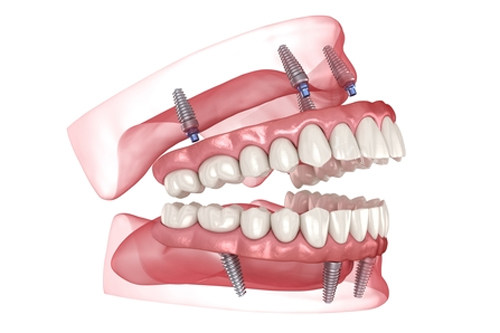

2025 种植牙价目表:透明收费,性价比凸显

汕头满珠口腔 2025 年种植牙收费项目清晰透明,从植体品牌到牙冠选择,都有明确的价格标注。韩系进口种植牙套餐价格为 4980 元起 ,这个价位在汕头种植牙市场中非常有竞争力。要知道,市面上部分口腔机构韩系种植牙起步价可能在 6000 元以上,满珠口腔以近千元的价格优势,让更多市民能够负担得起种植牙修复。

如果对种植体品质有更高要求,欧美进口种植牙套餐价格在 8800 元起 。该价位涵盖了海内外出名品牌的植体,这些植体与人体相容性好,使用寿命长。同时,满珠口腔还提供全口、半口种植牙方案,半口种植牙包干价在 35000 元起 ,相比一些高端口腔机构动辄七八万的价格,满珠口腔在确保技术和质量的前提下,大大降低了患者的经济压力。

无论是种植牙还是阻生齿拔除,满珠口腔都拥有正规的医疗团队和新型设备作为支撑。种植医生团队均有多年临床经验,熟练掌握各种复杂种植技术;口腔外科医生在阻生齿拔除方面技术娴熟,能够应对各类疑难实例。同时,诊所配备的智能化诊疗设备,如 3D 口腔扫描仪、智能化种植导板等,为精细治疗提供了有力确保。